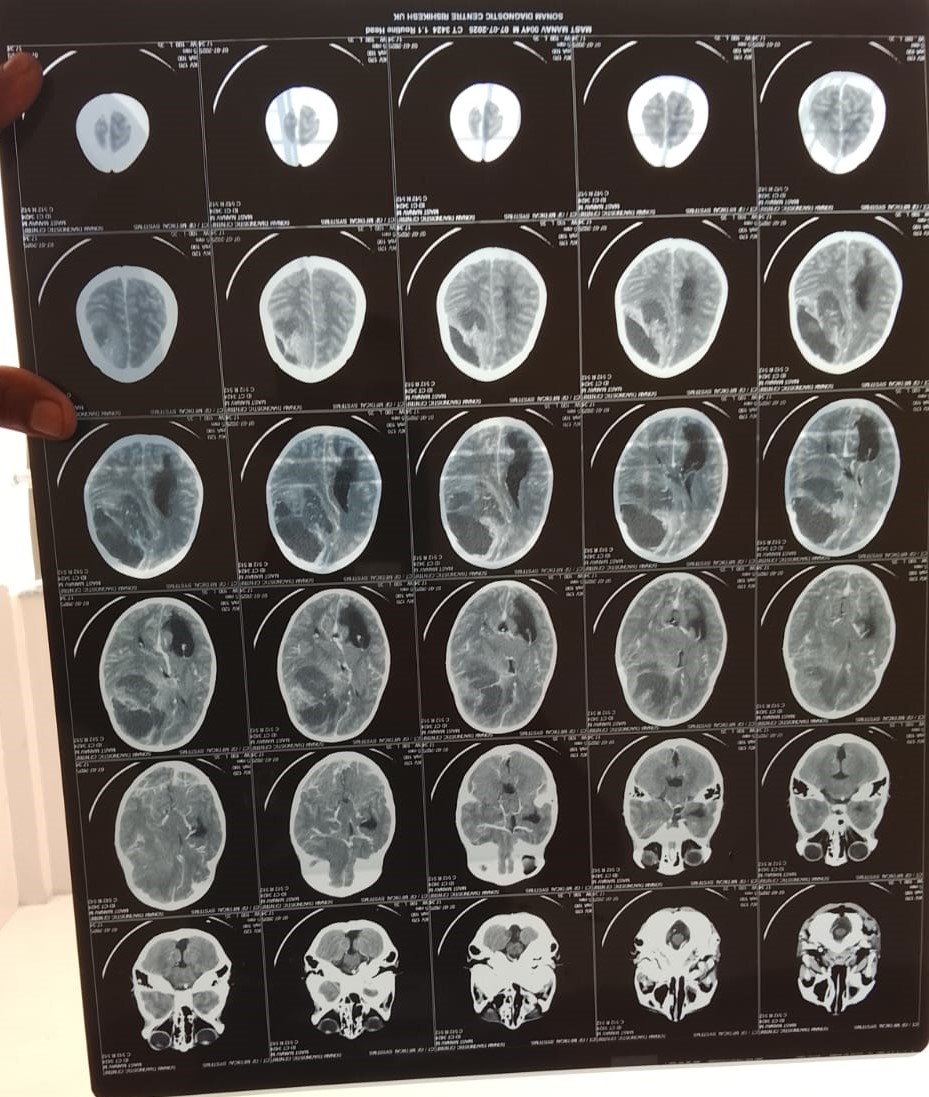

A Little Life Is in Danger – 4-Year-Old Manav Needs Your Urgent Help -We humbly appeal to your kindness and compassion to help save the life of Manav, a 4-year and 7-month-old child from village Sakni, Patti Bharpoor, Tehsil Devprayag, District Tehri Garhwal, Uttarakhand. Manav is currently battling a life-threatening brain tumor and is in critical condition.

Just a few days ago, Manav’s health started to deteriorate unexpectedly. He complained of severe headaches and vomiting. His parents took him for a medical check-up, and what followed was a devastating diagnosis — a large brain tumor that is causing swelling and pressure on his brain. Doctors immediately recommended urgent treatment, including brain surgery, with an estimated cost of ₹7 lakh.

Doctors at Jolly Grant Hospital, Dehradun, have advised immediate brain surgery, scheduled for 18th July 2025. Every hour matters now.